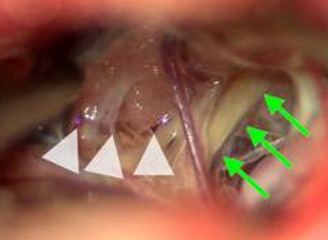

典型的には、脳槽といわれる、脳の周りの髄液という水がたまっている部分で、曲がりくねった動脈が三叉神経を圧迫して起こります。